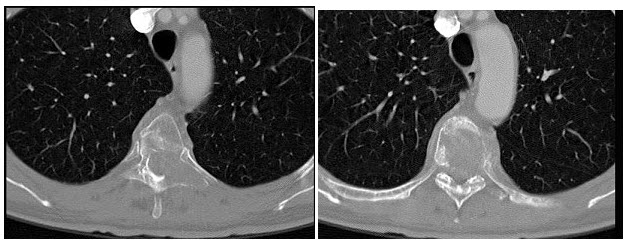

24、单项选择题

女,45岁,右腰部疼痛伴血尿,根据所示图像,最可能的诊断是()

A.右肾结核

B.右肾出血

C.右肾结石

D.右肾积水

E.右肾结石合并右肾扩张积水